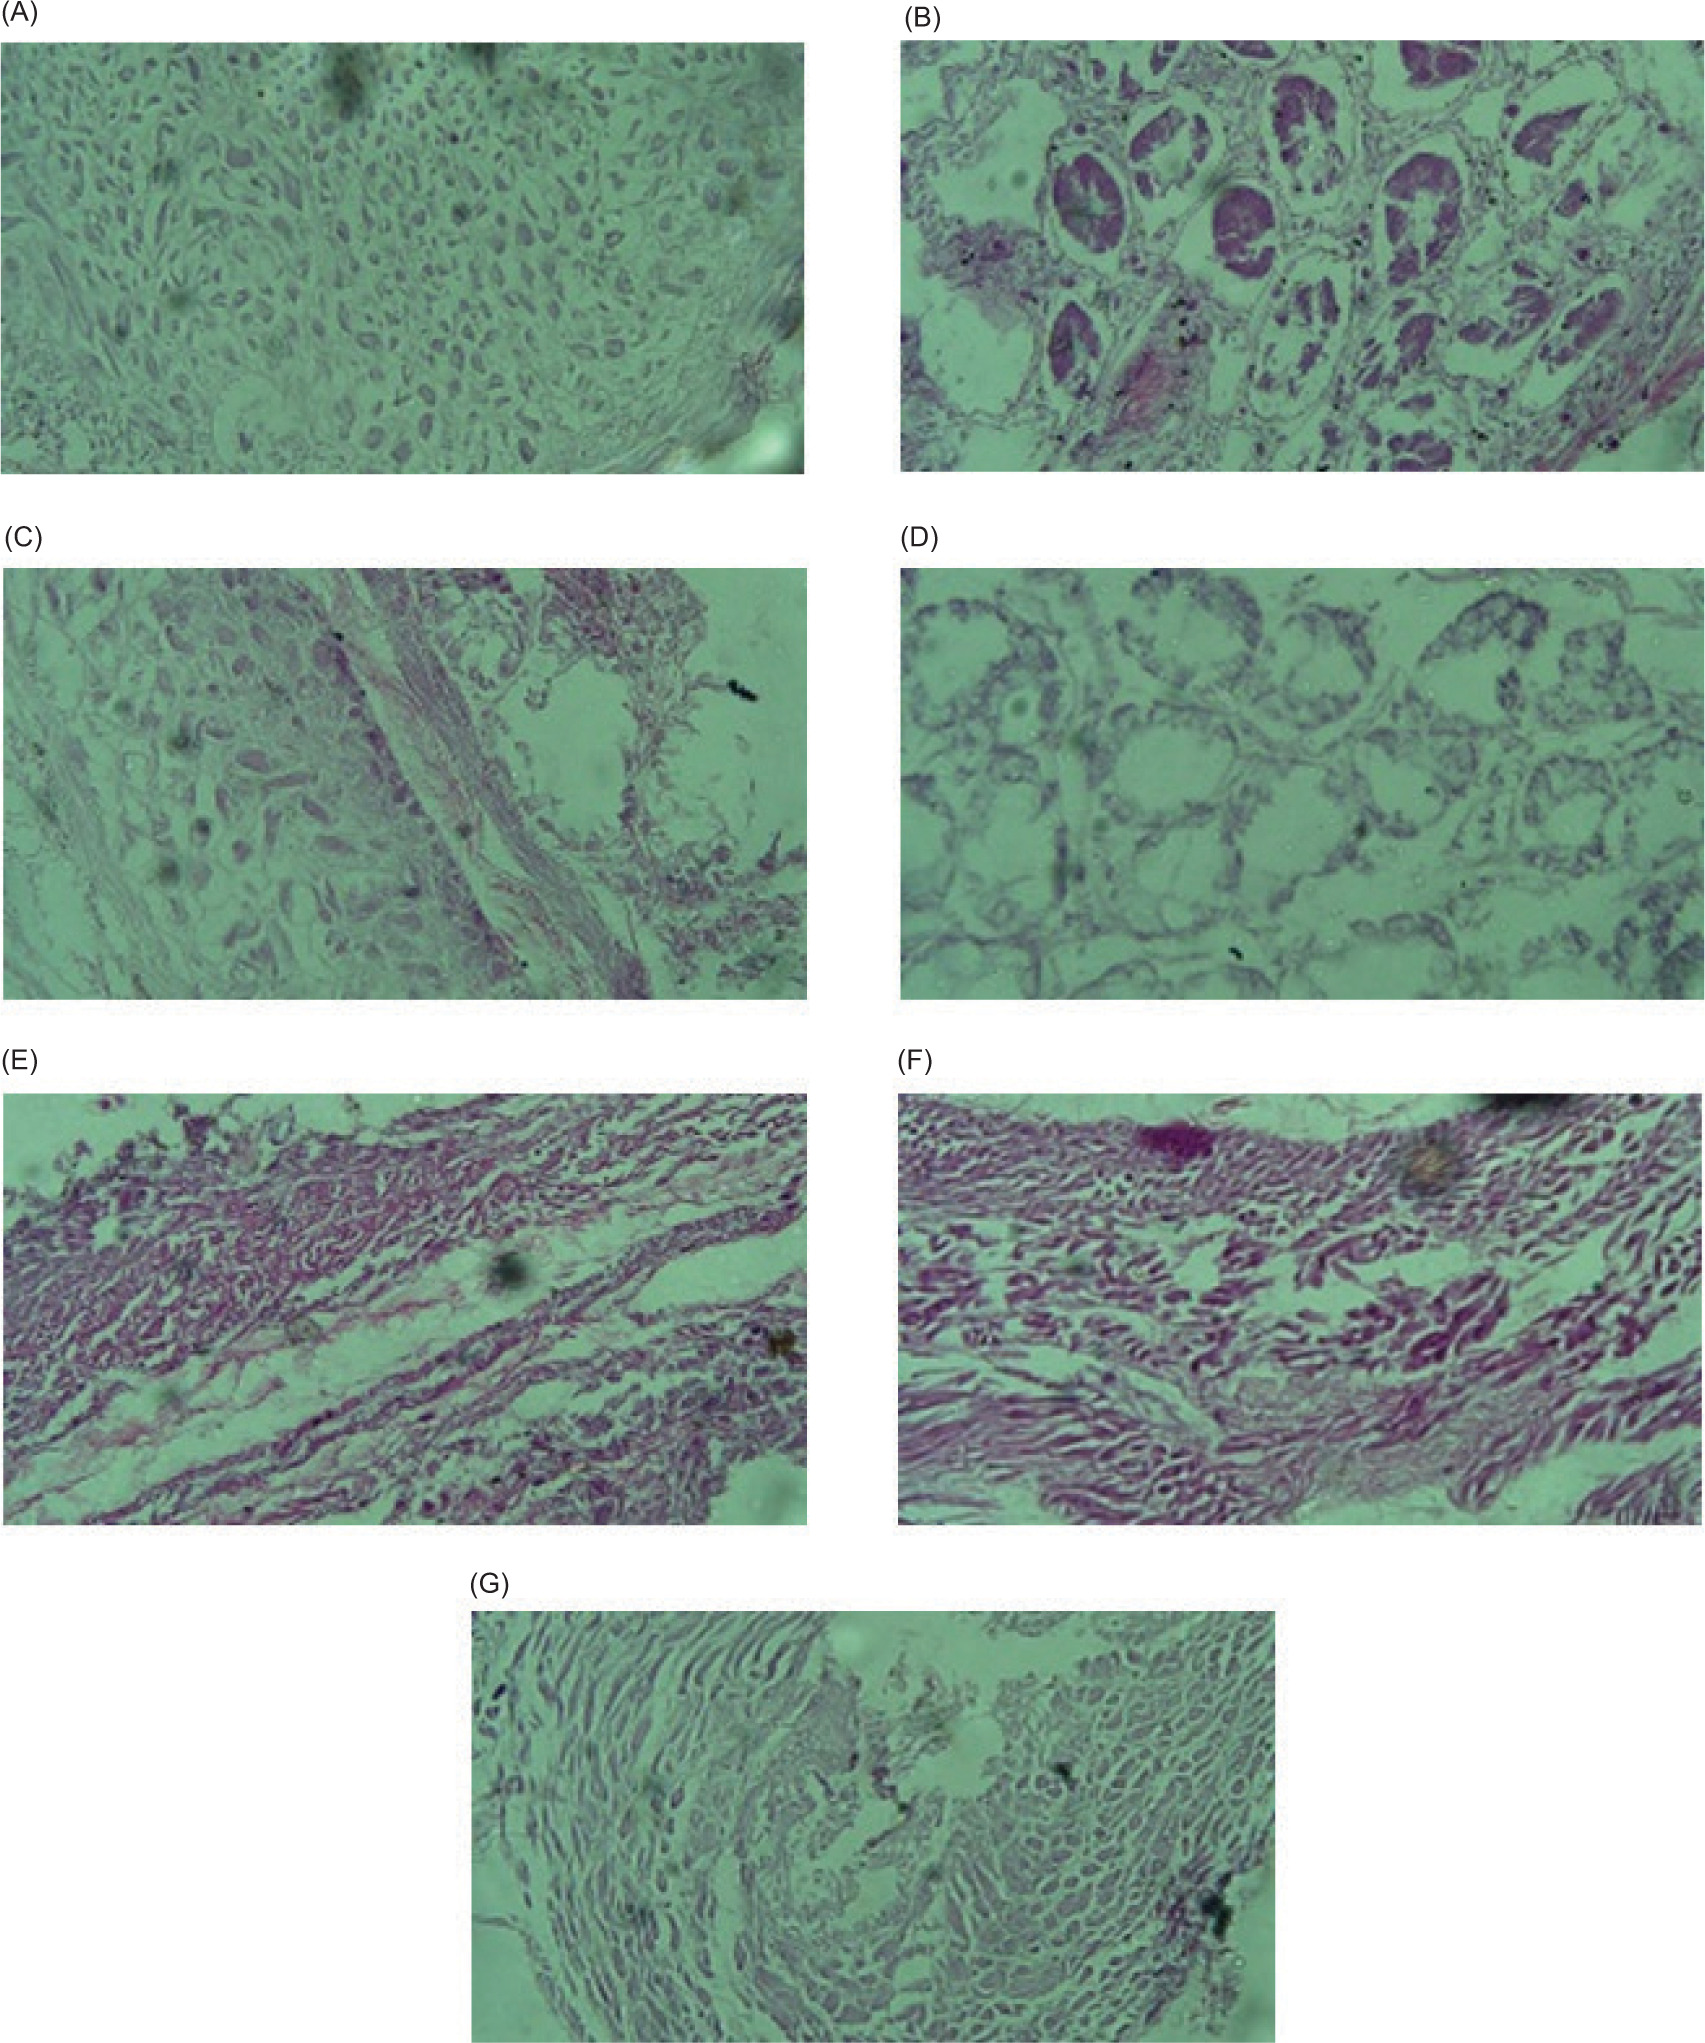

The analysis of liver histology showed mild to moderate toxic effects. The negative control group (G1) exhibited no changes in sinusoids, hepatic cords, and Kupffer cells. In the positive control group (G2, treated with 150-mg/kg alloxan), the histology of liver tissues revealed the existence of microvesicular fatty alterations throughout the acinus and central lobule, portal triad regions appeared less distinct/visible, and Kupffer cells exhibited sign of reactivity. In addition, mid-portal inflammation was observed and the central vein displayed well-differentiated features in histology of G2 animals. Nuclei structures were well formed and the hepatic lobules showed well-formed structures, with noticeable alterations in fatty microvesicular within the hepatic cords in histology of G3 (fed with 50-mg/kg PPE) animals. Also, G3 demonstrated regular orientation reactivity was observed in Kupffer cells and well-differentiated endothelial lining in the central vein with normal morphology. Similarly, in G4 (fed with 100-mg/kg PPE), liver histology revealed an arrangement of well-organized Kupffer cells and reactive changes. Well-organized hepatic cords demonstrated clear acinar microvesicular fatty changes, and proper endothelial lining was found in the central vein. The histology of G5 (fed with 150-mg/kg PPE) showed normal central vein and endothelial lining, with no fibrosis around blood vessels; a significant microvesicular fatty change from the central vein to portal triads and pan acinar microvesicular fatty changes were observed; reactive Kupffer cells and dilated sinusoid cells were also observed, with a healthy and normal central vein and well-formed hepatic cords. In G6 (fed with 200-mg/kg PPE), most hepatocytes showed microvesicular fatty alterations and normal nuclei; reactive Kupffer cells were observed in sinusoid walls that appeared relatively dilated with elevated bile pigment in their lumen. In G7 (fed with 50-mg/kg metformin hydrochloride), the central vein and endothelial lining were well formed, walls were not thickened, nuclei appeared normal, with reactive Kupffer cells and well-formed hepatic cords. The detailed data of all groups are shown in Figure 5.

Figure 5. Photomicrographs of the liver in diabetes-induced mice groups fed with PPE and metformin hydrochloride. (A) Negative control mice group, no alteration was observed in hepatic cords, Kupffer cells, or sinusoids; (B) positive control mice group (G2, treated with alloxan) showed microvesicular fatty changes, reactive Kupffer cells, mid-portal inflammation, portal triad and central lobule less visibility, intact nuclei, and well-differentiated central vein; (C) G3 (fed with 50-mg/kg PPE) showed hepatic lobules with distinct structures with evident fatty microvascular changes in the hepatic cords, intact Kupffer cell orientation, and normally formed endothelial lining in the central vein; (D) G4 (fed with 100-mg/kg PPE) showed well-organized Kupffer cells, and reactive changes. Well-organized hepatic cords demonstrated clear acinar microvesicular fatty changes, and proper endothelial lining was discovered in the central vein; (E) G5 (fed with 150-mg/kg PPE) showed healthy central vein and endothelial lining, with widespread microvesicular fatty changes throughout the acinar zones, reactive Kupffer cells, and dilated sinusoids; (F) G6 (fed with 200-mg/kg PPE) showed microvesicular fatty alterations with intact nuclei in hepatocytes, and dilated sinusoids with increased bile pigments activated Kupffer cells; (G) G7 (treated with metformin hydrochloride) showed well-formed hepatic cords, activated Kupffer cells, and intact endothelial lining of the central vein without thickened walls.